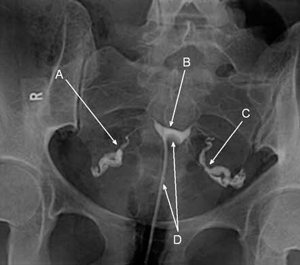

На снимката се вижда как контраста се вкарва в матката през катетър и маточната кухина и фалопиевите тръби изглеждат бели - (А:дясна тръба; В:маточна кухина; С: лява тръба; D: катетър).